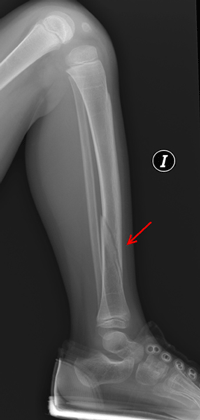

El diagnóstico prenatal se realiza por ultrasonografía en los tipos II y III, apreciándose fracturas prenatales y aumento de la translucencia. Las fracturas pueden detectarse desde las 14 semanas de embarazo en el tipo II y desde la semana 18 en el tipo III. (

Figuras 3 y

Figura 4). Las múltiples fracturas producen deformidad de huesos largos, costillas y cráneo. En el tipo IV ocasionalmente se realiza el diagnóstico sobre la semana 22 por acortamiento de huesos largos, sin fracturas ni osteopenia. La OI tipo I no se puede diagnosticar

Figura 3. Fractura de radio y cúbito (flechas).

Figura 4. Fractura distal de tibia (flecha) en el mismo paciente afecto

de osteogenesis imperfecta tipo 1.